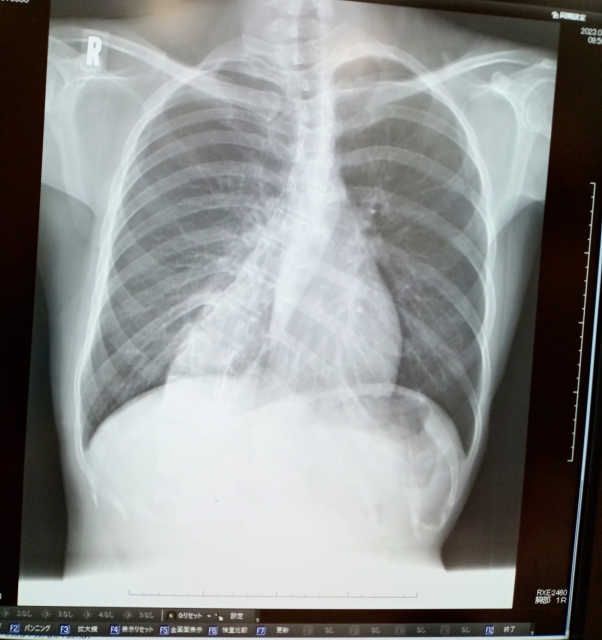

子供の側弯症:手術以外の選択肢と治し方 » 側弯症 背骨 レントゲン